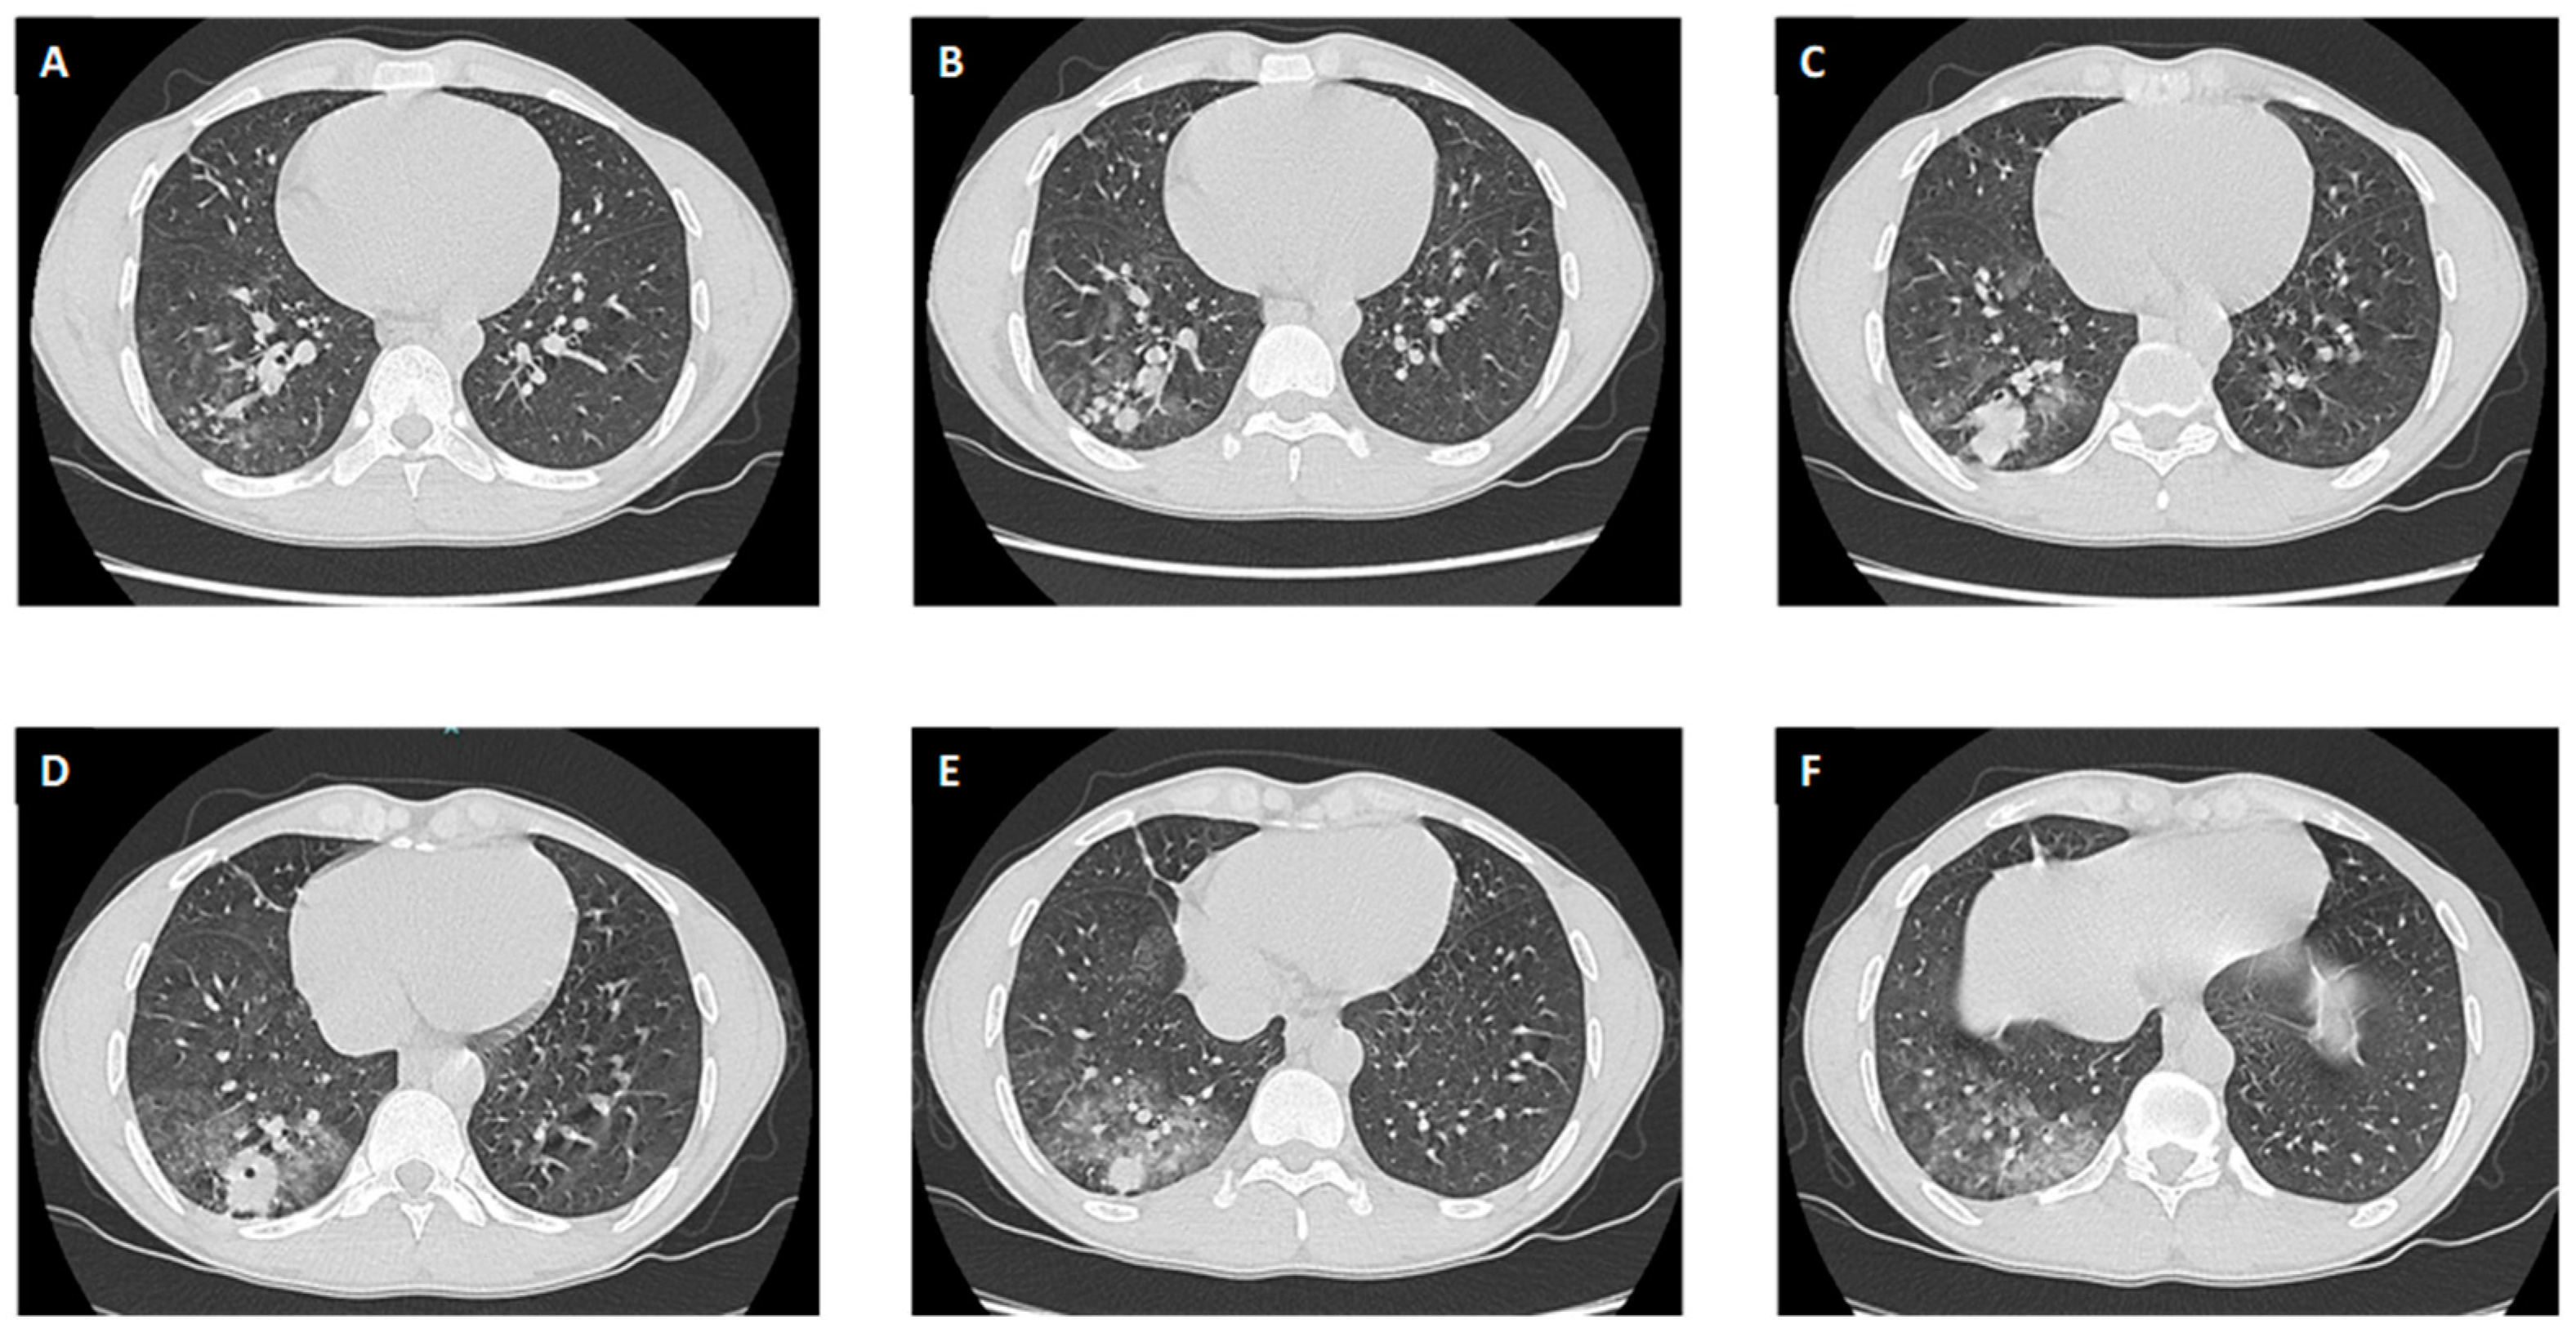

3.2.3. Radiological Findings